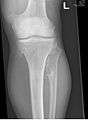

multiple osteochondromas around the knee- CT of osteochondroma in MO